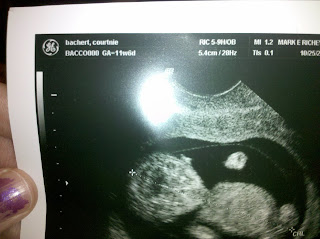

Here are some pictures from my last appointment that I had last week! The Doctor is very pleased with everything. He said I looked Golden! So far still No bed rest. My appointment that I had I was suppose to do do the gestational diabetes test. Which in tails drinking this HORRIBLE drink 30 minutes before your appointment well I was driving so I had to pull over half to Anchorage. I drank the whole thing and then it decided to come back up! All over myself and the truck. NOTE I locked the truck door because I didn't really know where I was. So when I need to throw up the door was locked. Lets just say it was an awesome way to start my day. So I couldn't complete the test. Now I have to do some Fasting and then go get my blood drawn. The Doctor isn't worried that I have it. But its a test that has to be done. My next appointment is on Koa's 5th Birthday! I cant believe his going to be 5 in two weeks. Time sure does fly. He is so excited about his birthday. He is counting down the days.